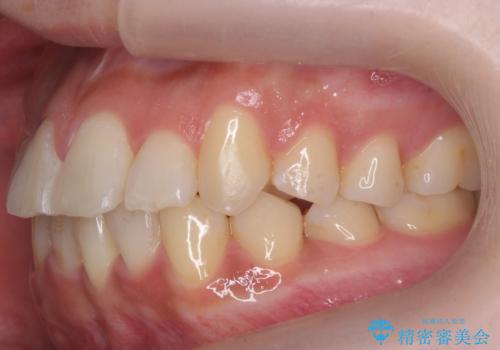

- 前歯のがたつき、受け口を主訴に来院。

上の前歯が二本裏側に入っていました。(反対咬合といいます)

全体矯正で治そうとすると非抜歯ですとだいぶ口元が前に突出するのに加え、下の前歯が入りきらない可能性がありました。上下左右4本抜歯となるため、それを回避するのに下の前歯を1本抜歯して、下の前歯を確実に内側に入れています。